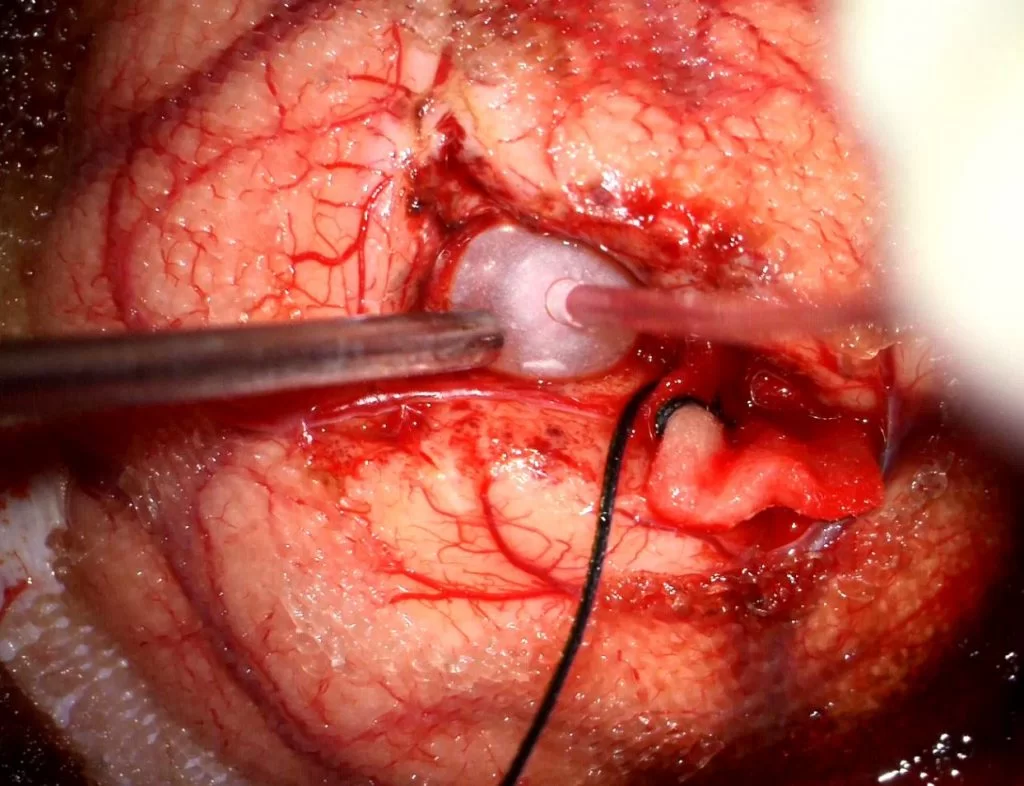

Διενεργήθη διαφλοιική προσπέλαση με τη βοήθεια νευροπλοήγησης και ολική (Simpson I) εξαίρεση της βλάβης.

Στη συγκεκριμένη περίπτωση, με τη βοήθεια του νευροπλοηγού και της μαγνητικής δεσμιδογραφίας επιλέξαμε μια οδό η οποία ήταν σύντομη , αποφεύγοντας ταυτόχρονα κρίσιμα νευρικά δεμάτια. Χρησιμοποιώντας ελάχιστα επεμβατικές τεχνικές ελαχιστοποιήσαμε το τραύμα στον εγκέφαλο (βλ. Διεγχ. Εικόνα η οποία δείχνει την τεχνική της διήνησης με μπαλονάκι – balloon dissection).